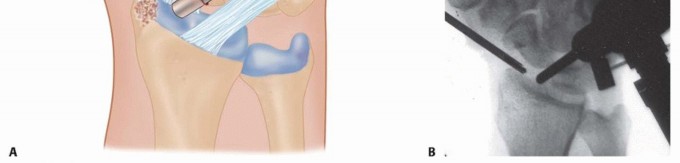

Image

Once the sensory nerves are safely isolated, the deep antebrachial fascia is incised. The surgical interval is developed between the first dorsal compartment (APL and EPB) and the second dorsal compartment (ECRL and ECRB). The first compartment is retracted volarly, and the second compartment is retracted dorsally using small right-angle retractors (e.g., Senn or Ragnell retractors). This exposes the underlying joint capsule and the periosteum of the distal radius. A longitudinal or inverted T-shaped capsulotomy is performed directly over the radial styloid. The capsular flaps are elevated subperiosteally to expose the entire lateral aspect of the styloid and the radioscaphoid articulation.

With the joint exposed, the precise location of the impingement is visually confirmed by taking the wrist through a range of motion, particularly radial deviation and extension. The osteotomy is then performed. A micro-sagittal saw or a sharp, thin osteotome is utilized. The cut is initiated on the lateral extra-articular cortex, no more than 3 to 4 millimeters proximal to the tip of the styloid. The blade is directed obliquely, aiming distally and ulnarly to exit precisely at the junction of the styloid and the scaphoid fossa. During the osteotomy, a Freer elevator or a small Hohmann retractor is placed intra-articularly to protect the articular cartilage of the scaphoid from iatrogenic injury.